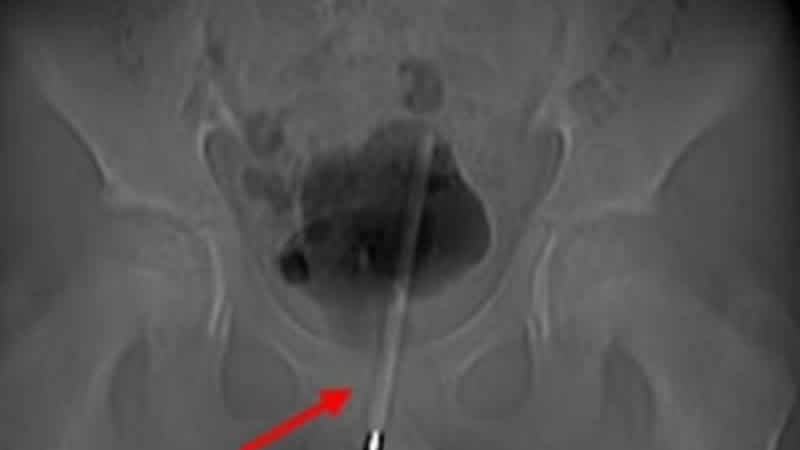

Çekilen röntgen, termometrenin idrar yoluna kadar sokulduğunu ve çocuğun mesanesine girdiğini ortaya çıkardı.

Asian Journal of Surgery’de vakayı detaylandıran ürologlar, mesaneye giden dokuda küçük bir cerrahi delik açtıklarını ve ardından termometreyi doğru konuma getirerek onu çıkarmak için küçük aletler kullandıklarını söyledi.